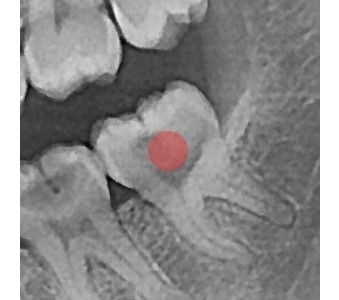

결과로 증명합니다.

국제모아치과의

실제 임상 증례